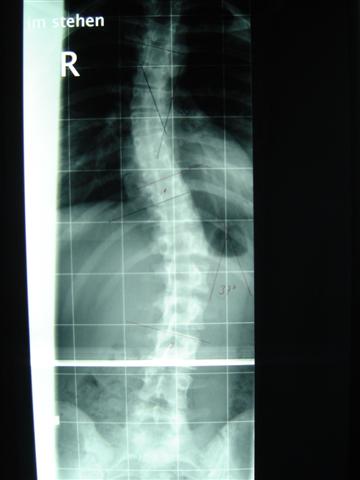

ich war heute in Dresden zum Röntgen gewesen. Musste erst zur Anmeldung, den Schein fürs Röntgen holen und dnan zum Röntgen gehen. Dort stand oben, das ich nur im Tgaeskorsett geröngt werden soll. Wir uns dann beschwert, weil aj nciht im Nachtkorsett geröngt wurde. Also ham se bei der Anmdelung vom dem Orthopädiehaus angerufen und ich konnte doch noch geröngt werden. Und als der Oberarzt die Röbis vermessen hat konnte er es fast selber nicht fassen!! Mein Tgaeskorsett korrigiert die lumbale Krümmung von 37° auf 12° !!!!! Ihr könnt euch gar nicht vorstellen, wie happy ich in dem Moment war, weil ich da die ganze Zeit an Fine und ihre Korsetts denken musste. Meine obere Krümmung wird im Tageskorsett nicht korrigiert, weil diese sehr weit oben sitzt und mein Arm einschläft, wenn er angehoben wird. Aber von den 34° ohne Korsett sind 28° es steht zwar 18° auf dem röbi, aber der Unterschied zu den 12° ist doch zu groß. Wir haben die Röbis auch fotografiert, ich stelle die Bilder dann demnächst hier rein. Im Nachtkorsett ist die untere Krümmung 13 °, und weil die irgendiwe im Liegen nicht die ganze WS röntgen können, kann die obere nicht vermessen werden :boese: und grade das würde mich mla interessieren, weil die ja im Tageskorsett nicht wirklich korrigeirt wird. Trotzdem hab ich mich sp über 12° gefreut, dass ich dann noch 0,5cm Polster hab hochmachen lassen. Mehr wollte der OT nicht, aber ich merke doch schon eine Veränderung. :)

Noch mal die Werte im Überblick:

1. Röntgen, 1.3.05: 29° im BWS-Bereich, 32° in der LWS

2. Röntgen, 25.4.05: 34° in der BWS und 37° in der LWS (beides um 5 grad verschlechtert, die Ärzte hatten mir nicht mehr zu viel Hoffnungen gemacht)

3. Röntgen im Korsett, 29.8.05: 28° und 12° :freude:

Ich häng auch mal die Röbis ran.

1.OhneKorsett 1.JPG

1.OhneKorsett 1.JPG (19.58 KiB) 9663 mal betrachtet